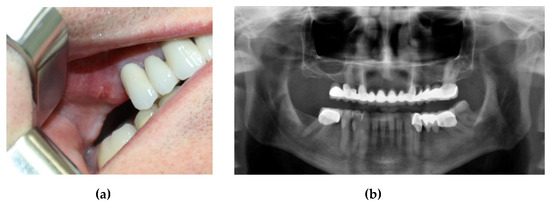

This case involved a 50-year-old male patient who presented to the clinic with a maxillary cantilever cemented prosthetic restoration. The patient affirmed that the functional role of this restoration became completely inadequate, with no possibility of mastication on the right side. The first step of the procedure included a clinical examination (Figure 1), where the missing maxillary right first and second molars were remarked. The first molar was extracted two years ago and the second molar over ten years ago. The intraoral examination showed a healthy gingival and mucosal status. For an accurate diagnosis, a radiological evaluation was performed. The treatment options were explained, and the patient was also informed about the benefits and risks of each treatment option. As he wanted to avoid a removable prosthesis due to its inconvenience, the chosen treatment option was an implant-supported crown restoration.

Figure 1. (a) Initial clinical assessment; (b) preoperative orthopantomogram (OPG) showing an insufficient height for implant insertion in the maxillary right first molar edentulous site.